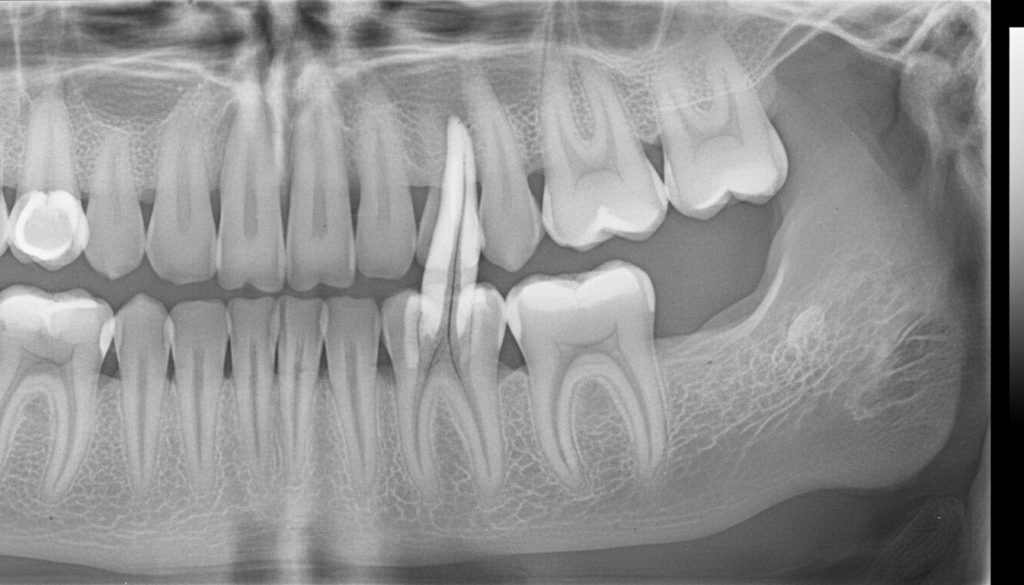

歯科用CTによる正確な診断

歯科用CTは3次元の立体画像で歯のレントゲンを撮ることができる装置です。

根管は複雑な形状であるうえ、歯によっては数本に分岐しています。

平面のレントゲン画像では確認できない細部も、歯科用CTの立体画像なら詳細に把握できるため、より一層精密な診査診断、治療が可能になります。

自覚症状はなくてもレントゲンでみつかることがあります。